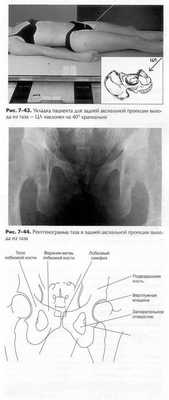

ЗАДНЯЯ АКСИАЛЬНАЯ ПРОЕКЦИЯ ВХОДА В ТАЗ 1 : ТАЗ

![]() |

Пациент лежит на спине, под голову кладется подушка. Ноги пациента вытянуты, для удобства под колени пациента ставят опору.

• Срединная сагиттальная плоскость выравнивается по ЦЛ

и средней линии стола и/или кассеты.

• ЦЛ наклонен каудально на 40° (почти перпендикулярен плос

кости входа в таз).

• ЦЛ направлен к точке средней линии, соединяющей обе

ВППО.

• Минимальное РИП составляет 100 см.

Диафрагмированиевыполняется с четырех сторон близко к

области интереса.

Критерии оценки рентгенограммы Видимые анатомические структуры.* Эта аксиальная проекция хорошо демонстрирует тазовый пояс или вход в таз (верхнюю апертуру) в целом.

Укладка.• Об отсутствии ротации свидетельствует полная видимость обеих подвздошных остей, одинаковых по размеру и форме.

Диафрагмирование и ЦЛ.• О правильности угла и направления ЦЛ свидетельствует наложение друг на друга переднего и заднего отделов тазового кольца. • С центром поля диафрагмирования должен совпадать центр входа в таз. • Боковые края поля диафрагмирования должны быть равными с обеих сторон от головок бедренных костей и вертлужных впадин. Сверху и снизу поле диафрагмирования должно захватывать крылья и симфиз.

Параметры экспозиции.• Оптимальная экспозиция демонстрирует наложенные друг на друга передний и задний отделы тазового кольца. Обычно имеет место переэкспонирование боковых сторон крыла. Четкие контуры костей и отчетливая трабекулярная структура лобковой и седалищной костей указывают на отсутствие движения во время экспозиции.